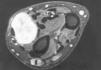

Los lipomas fueron los tumores de mayor tamaño de la serie, siendo el tamaño medio de 3,3 * 2,7 cm (máximo: 6,6 * 6 y mínimo: 0,7 * 0,5 cm). Dado el gran tamaño que pueden alcanzar en la palma, la afectación de varios radios fue frecuente. En las comisuras fue habitual que el crecimiento tumoral traspasara al compartimento dorsal. El tamaño de los lipomas ubicados en las eminencias fue en algunos casos muy considerable; un lipoma hipotenar llegó a pesar 95 gramos. A pesar de su gran tamaño, estos tumores eran indolentes, multilobulados, adaptándose en su crecimiento a las estructuras adyacentes. Independientemente de localizarse en zonas con pedículos vasculonerviosos como el canal de Guyon, no ocasionaron déficit sensitivomotores en ningún caso.

La RM fue típica, apareciendo imágenes homogéneas de aumento de intensidad de señal en T1 (Fig. 4). Los casos en los que se llevó a cabo RM con reconstrucción tridimensional ésta permitió ubicar el tumor en su entorno, facilitando su resección (Fig. 5).

Las características arriba mencionadas respecto de la localización, tamaño y dificultad de delimitación obligan a la realización de estudios de RM, que demuestran un patrón típico de aumento de señal homogéneo en las secuencias potenciadas en T1 (Fig. 4).10,17,29 Dados los resultados y la utilidad de la RM en muchos de los casos de esta serie, su realización se recomienda sobremanera.

Figura 4. Lipoma hipotenar. Corte transversal de RM potenciada en T1 en la que se aprecia la relación de la tumoración con las estructuras vasculonerviosas y tendinosas palmares, así como digitaciones intermetacarpianas.